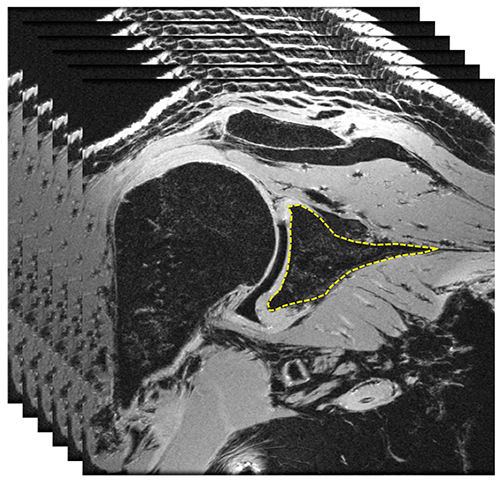

3D MR images of the shoulder are analyzed to isolate the region of glenoid.

Using image processing, 3D model of the glenoid is created.